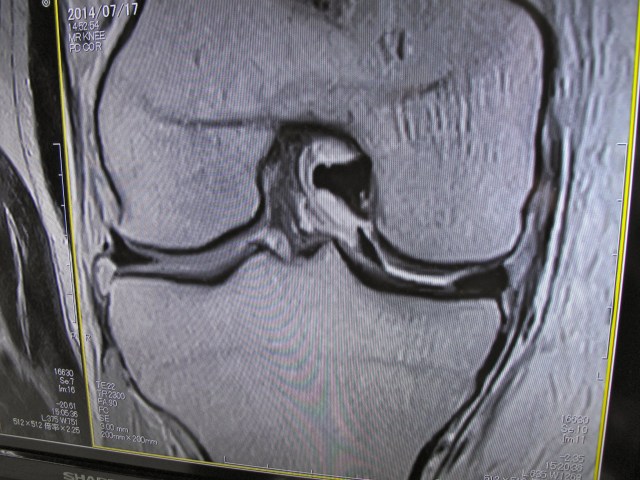

OK, this is a slice across my knee generated by the MRI. Thank you physicists. In the gap between the two bones, on the right hand side, you can see two black areas. essentially they should be one such as you see on the left hand side of the gap. This indicates a bucket-handle tear to the meniscus. How cool is that?